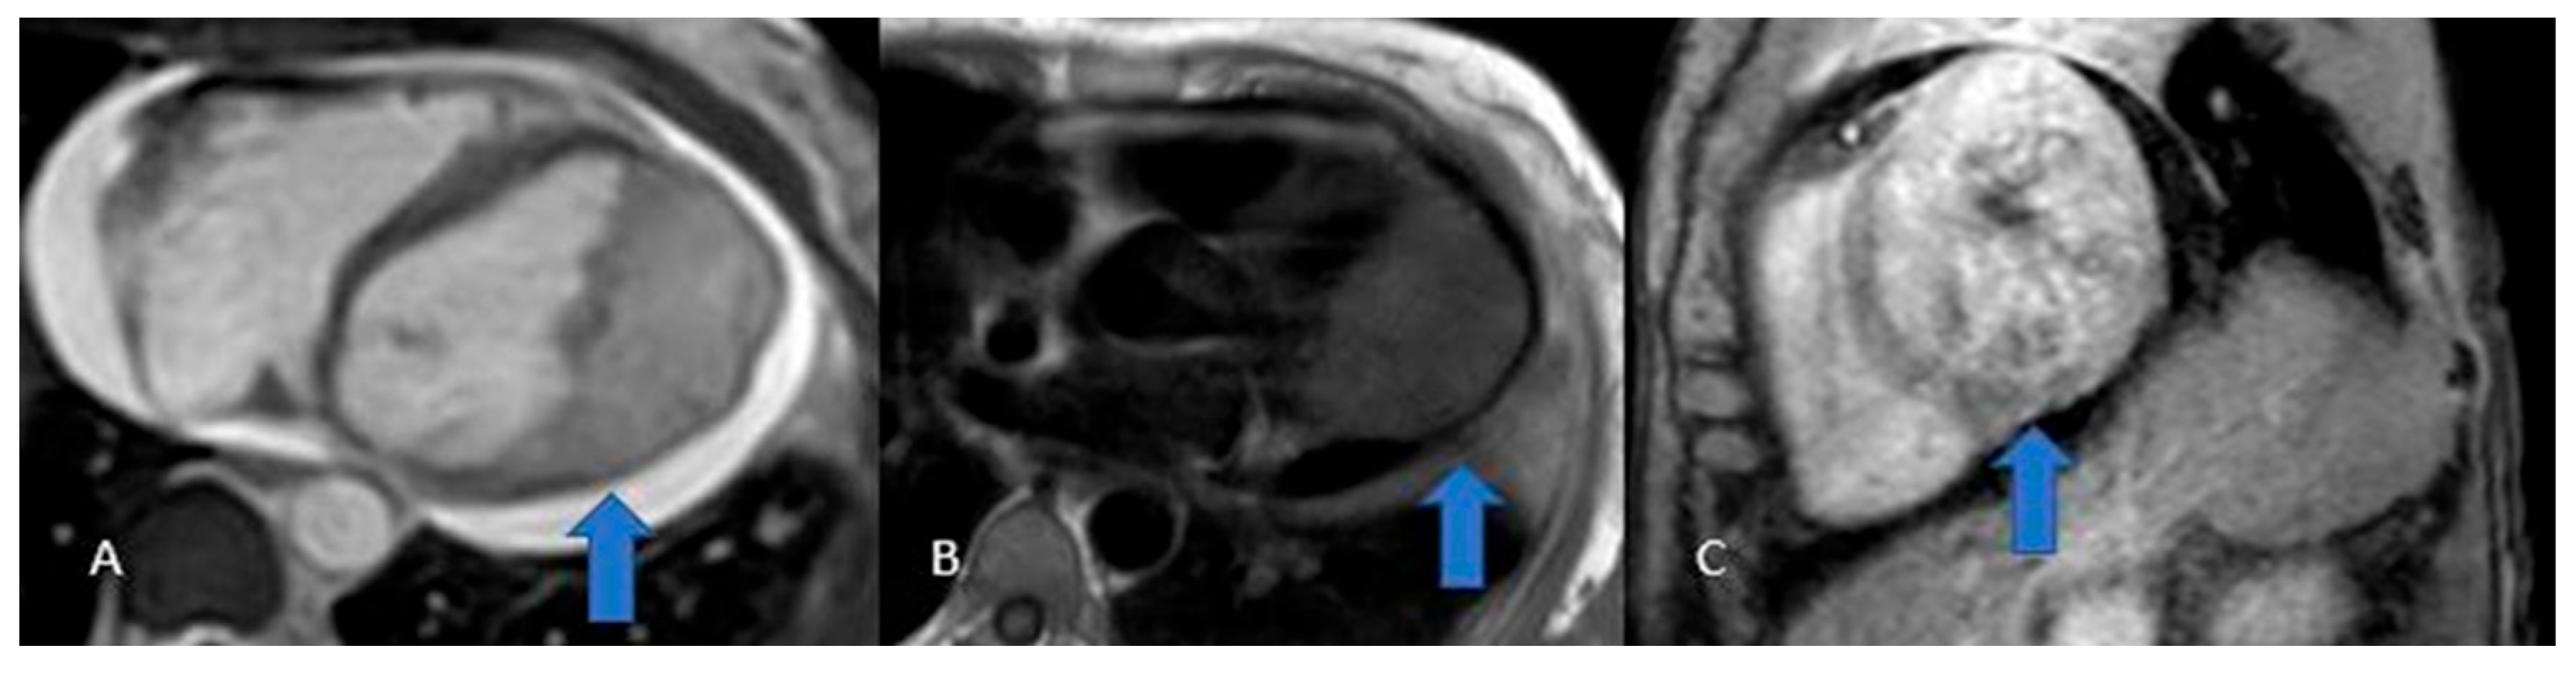

Figure 3. Thrombus (white arrows). CINE (A), EGE (B), and LGE (C) sequences show a large thrombus (arrows) at the apex of the left ventricle. Note that it remains hypointense and does not take up contrast, which is typical of thrombi and helps in distinguishing them from other cardiac masses.

3.1. Thrombi

Thrombi reveal themselves as non-opacified (“vacuum”) areas after contrast injection (Figure 3)—critical to recognize for proper treatment—and are classically found in the left atrium of patients with atrial fibrillation. On CT they appear as hypodense, non-enhancing lesions [29]; on MRI their signal shifts with age: acute clots display intermediate intensity on both T1 and T2 (due to oxyhemoglobin), subacute thrombi become T1-dark and T2-bright as hemoglobin converts to methemoglobin and draws in water, and chronic, fibrosed clots lose water, appear dark on both T1 and T2, and generally lack contrast uptake (though longstanding fibrotic thrombi can show rim enhancement on delayed sequences), similar to normal fibrotic tissue [2,3,12,30].